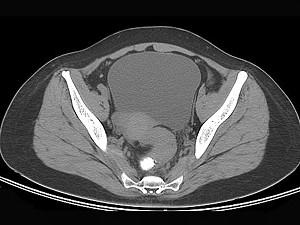

问题 男,67岁,排便习惯改变,血便三个月入院,CT检查如图所示,下列说法错误的是 ( )

选项 A、此为直肠息肉 B、此为直肠癌 C、其表面欠光整,边界欠清晰 D、可做直肠指检及活检以确定病变性质 E、直肠肠腔局限性增厚

答案 A